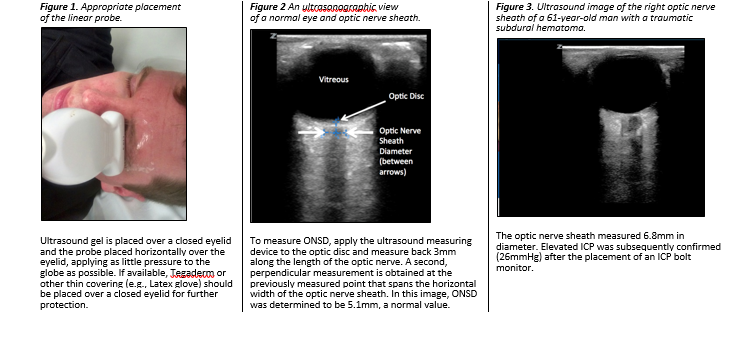

Ultrasonic Assessment of Optic Nerve Sheath Diameter

If a patient is unconscious (i.e. does not follow commands or open eyes spontaneously), they may have elevated ICP. There is no reliable test for elevated ICP available outside of a hospital; however, optic nerve sheath diameter (ONSD) measurement is a rapid, safe, and easy-to-perform ultrasonographic assessment that may help identify elevated ICP when more definitive monitoring devices are not available.

• The optic nerve sheath directly communicates with the intracranial subarachnoid space. Increased ICP, therefore, displaces cerebrospinal fluid along this pathway. Normal ONSD is 4.1–5.9mm.30

• A 10–5-MHz linear ultrasound probe can be used to obtain ONSDs. ONSD is measured from one side of the optic nerve sheath to the other at a distance of 3mm behind the eye immediately below the sclera.31

• In general, ONSDs >5.2mm should raise concern for clinically significant elevations in ICP in unconscious TBI patients.5,32 The ONSD can vary significantly in normal individuals, so one single measurement may not be helpful; however, repeated measurements that detect gradual increases in ONSD over time may be more useful than a single measurement.

• ONSD changes rapidly when the ICP changes, so it can be measured frequently.33 If ONSD is used, it is best to check hourly along with the neurologic examination.

Technique

1. Check to make sure there is no eye injury. A penetrating injury to the eyeball is an absolute contraindication to ultrasound because it puts pressure on the eye.

2. Ensure the head and neck are in a midline position. Gentle sedation and/or analgesia may be necessary to obtain accurate measurements.

3. Ensure the eyelids are closed.

4. If available, place a thin, transparent film (e.g., Tegaderm; 3M, http://www.3m.com) over the closed eyelids.

5. Apply a small amount of ultrasound gel to closed eyelid.

6. Place the 10(–5) MHz linear probe over the eyelid. The probe should be applied in a horizontal orientation (Figure 1) with as little pressure as possible applied to the globe.

7. Manipulate the probe until the nerve and nerve sheath are visible at the bottom of screen. An example of a proper ultrasonagraphic image of the optic nerve sheath can be seen in Figure 2.

8. Once the optic nerve sheath is visualized, freeze the image on the screen.

9. Using the device’s measuring tool, measure 3mm back from the optic disc and then obtain a second measurement perpendicular to the first. The second measurement should cover the horizontal width of the optic nerve sheath (Figure 2). An abnormal ONSD is shown in Figure 3.

10. Repeat the previous sequence in the opposite eye. Annotate both ONSDs on the PFC Casualty Card.

11. ONSDs should be obtained, when possible, at regular intervals to help assess changes in ICP, particularly when the neurologic examination is poor and/or unreliable (i.e. with sedation). Serial measurements with progressive diameter enlargement and/or asymmetry in ONSDs should be considered indicative of worsening intracranial hypertension.

CAUTION: ONSD measurements are contraindicated in eye injuries. NEVER apply pressure to an injured eye.